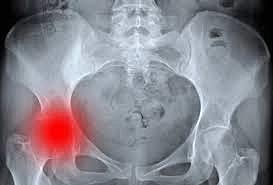

la aparición de otro tipo de complicaciones. el mayor problema derivaba de la erosión del hueso al lado acetabular, por lo que se desarrollaron nuevos implantes con recambio tanto del componente femoral como del acetabular. Nacía así la era de las artroplastias totales de cadera.